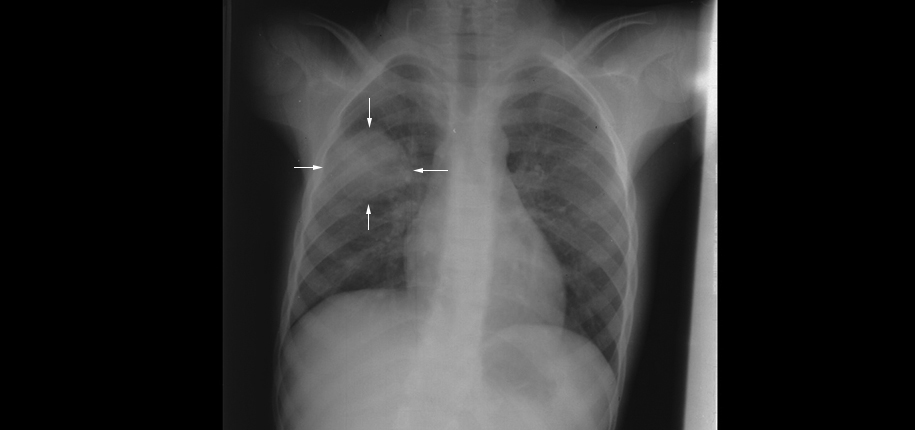

For this type of pneumonia performing a chest x-ray on the. Chest x-rays can reveal areas of opacity seen as white which represent consolidation. In complicated cases of pneumonia perform chest radiography 6 weeks after treatment to verify resolution of the pneumonia and to screen for any underlying predisposing.

Doctors typically rely on a physical exam and tests. Pulmonary consolidation is a non-specific term for pulmonary opacities seen on radiography that are the result from a process that fills the alveolar spaces further discussion here. Baby chest x ray pneumonia.

This chest X-ray shows an area of lung inflammation indicating the presence of pneumonia. However chest X-ray examinations for pneumonia detection are prone to subjective variability 2 3. Please see disclaimer on my website.

It determines the pathogen that could have caused pneumonia. The differential for the radiologic finding of pulmonary consolidation includes blood pulmonary hemorrhage pus infection ie. We investigate whether chest radiographic findings could be used as predictors of severity of childhood pneumonia.

The Radiological Diagnosis Of Pneumonia In Children Pneumonia Full Text

The Radiological Diagnosis Of Pneumonia In Children Pneumonia Full Text